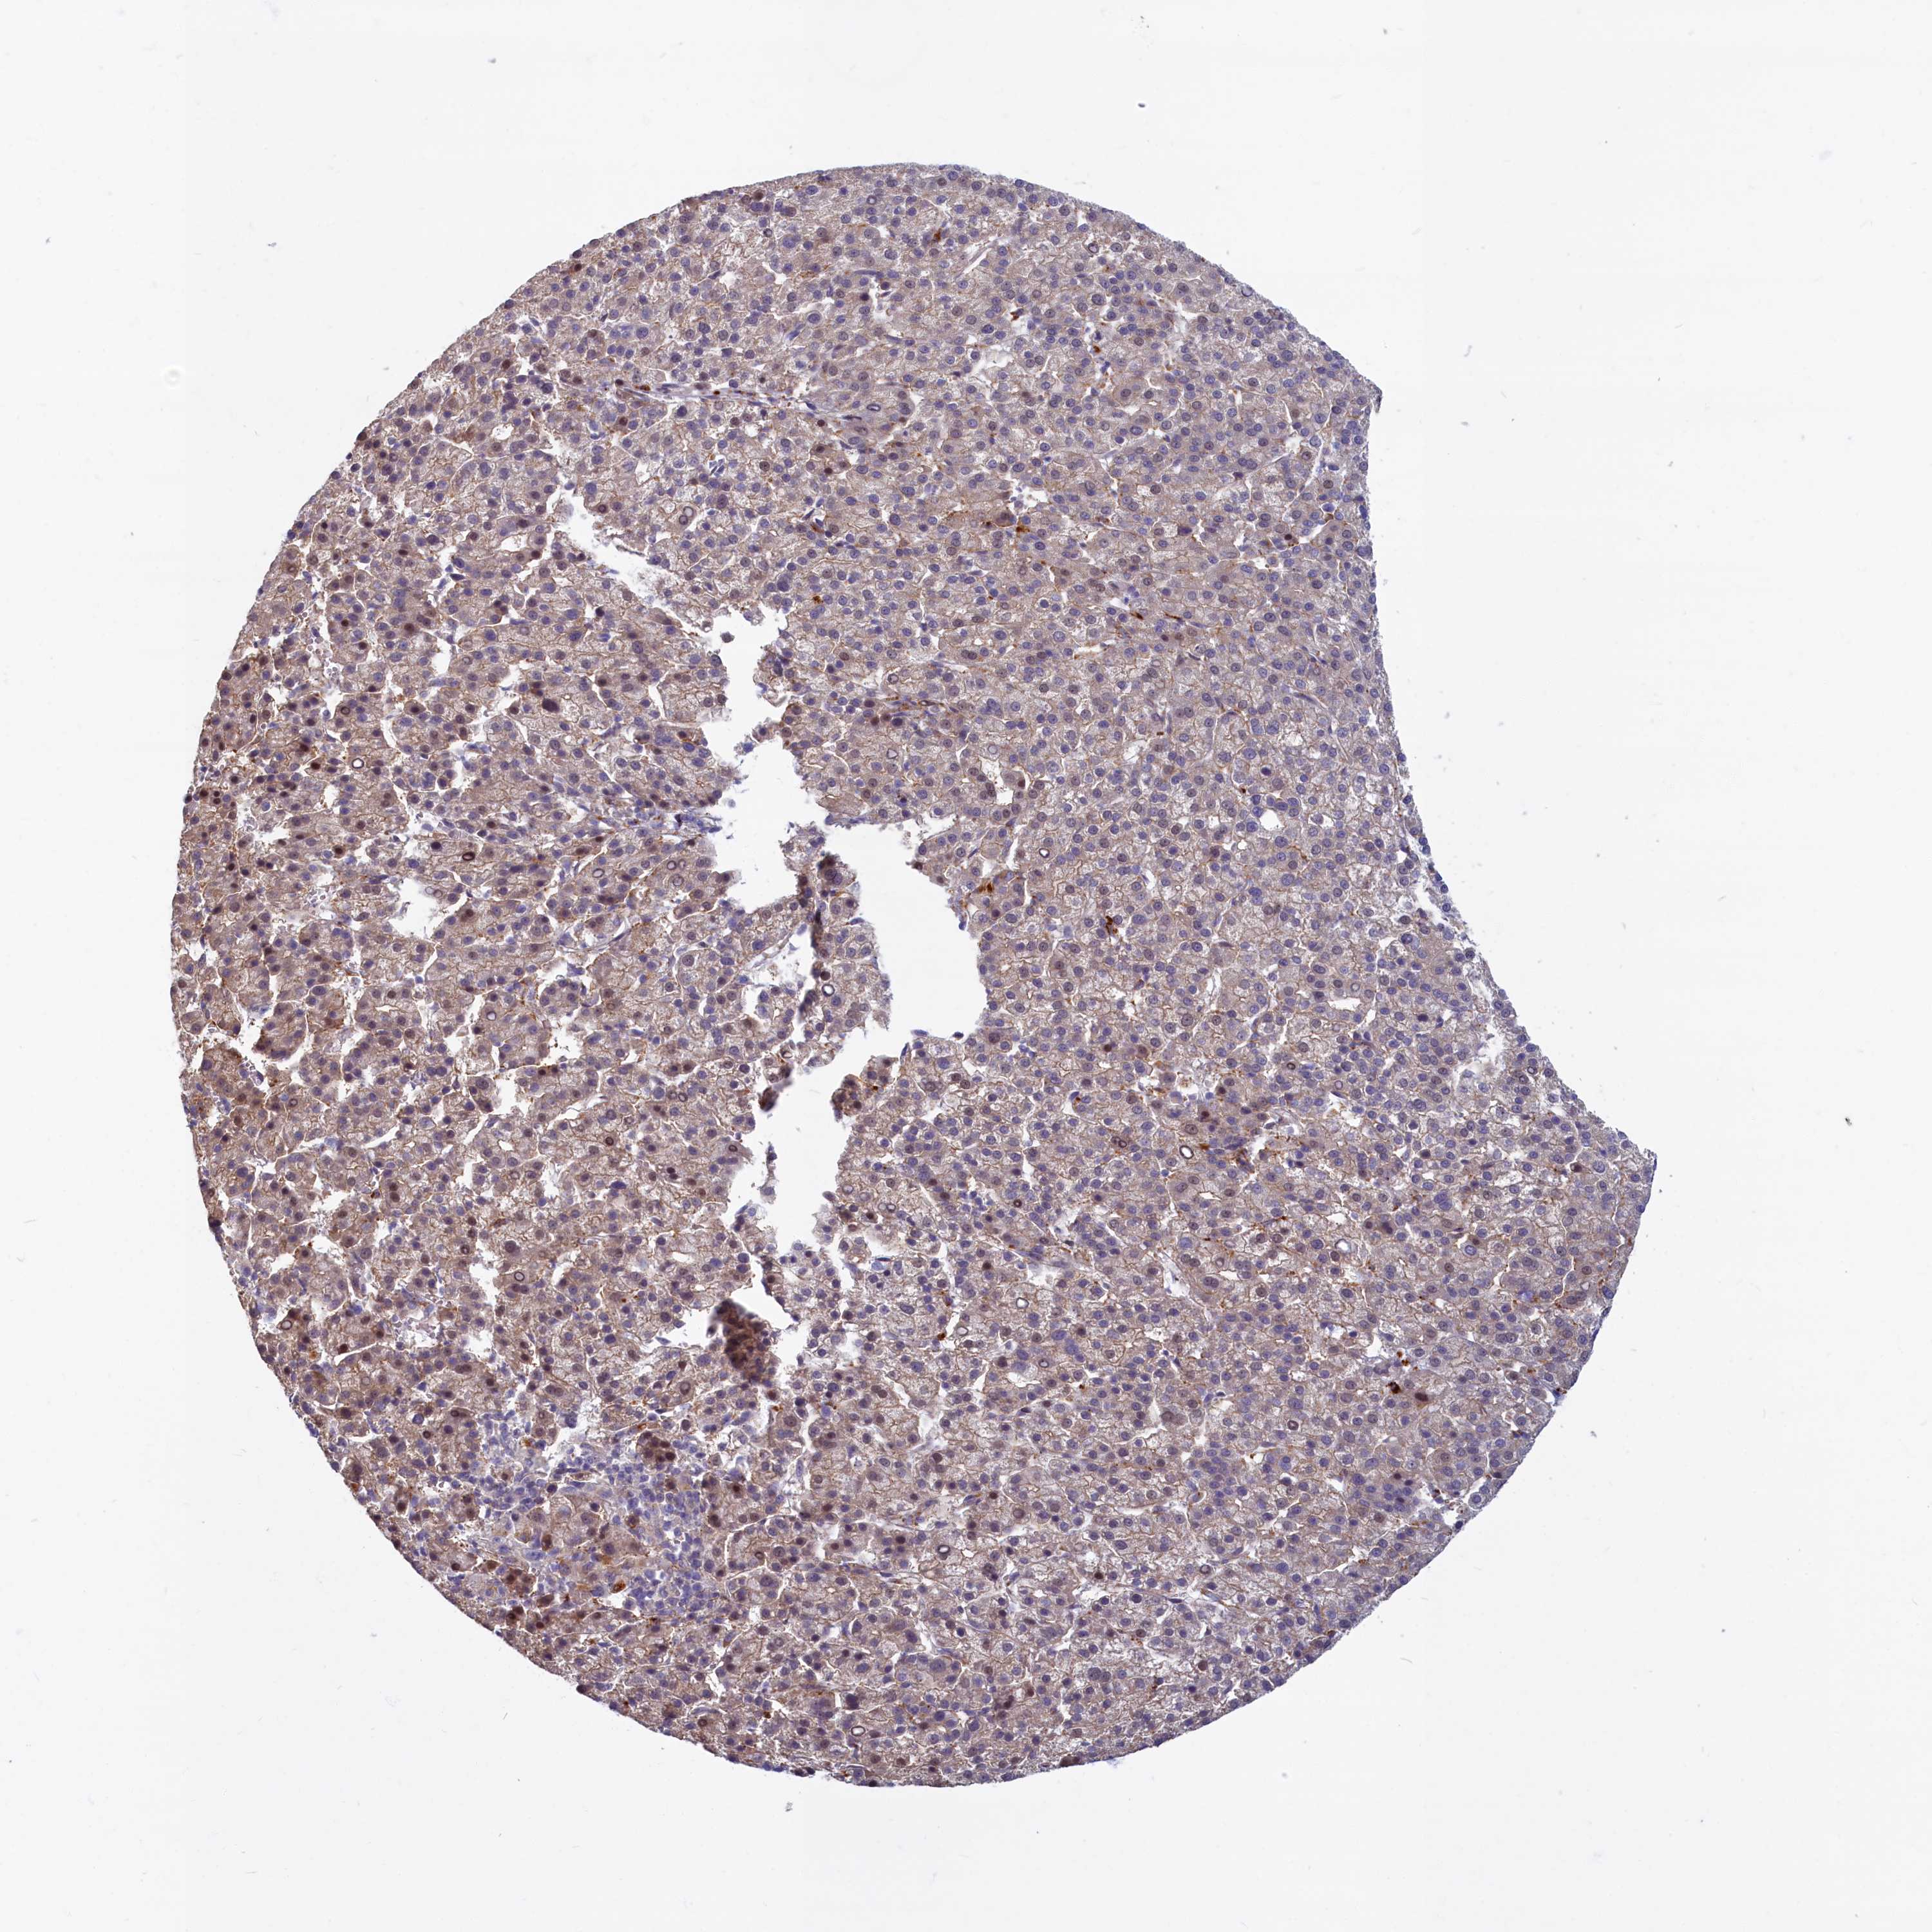

LIVER CANCER - Protein expressioni

A mouse-over function shows sample information and annotation data. Click on an image to view it in a full screen mode. Samples can be filtered based on level of antibody staining by selecting one or several of the following categories: high, medium, low and not detected. The assay and annotation is described here.

Note that samples used for immunohistochemistry by the Human Protein Atlas do not correspond to samples in the TCGA dataset.

Antibody stainingi

Antibody staining in the annotated cell types in the current human tissue is reported as not detected, low, medium, or high, based on conventional immunohistochemistry profiling in selected tissues. This score is based on the combination of the staining intensity and fraction of stained cells.

Each image is clickable and will lead to virtual microscopy that enables deeper exploration of all samples and also displays staining intensity scores, fraction scores and subcellular localization as well as patient and tissue information for each sample.

Antibody HPA041971

Staining

High

Medium

Low

Not detected

Intensity

Strong

Moderate

Weak

Negative

Quantity

>75%

75%-25%

<25%

None

Location

Nuclear

Cytoplasmic/membranous

Cytoplasmic/membranous,nuclear

Cholangiocarcinoma

Carcinoma, Hepatocellular, NOS